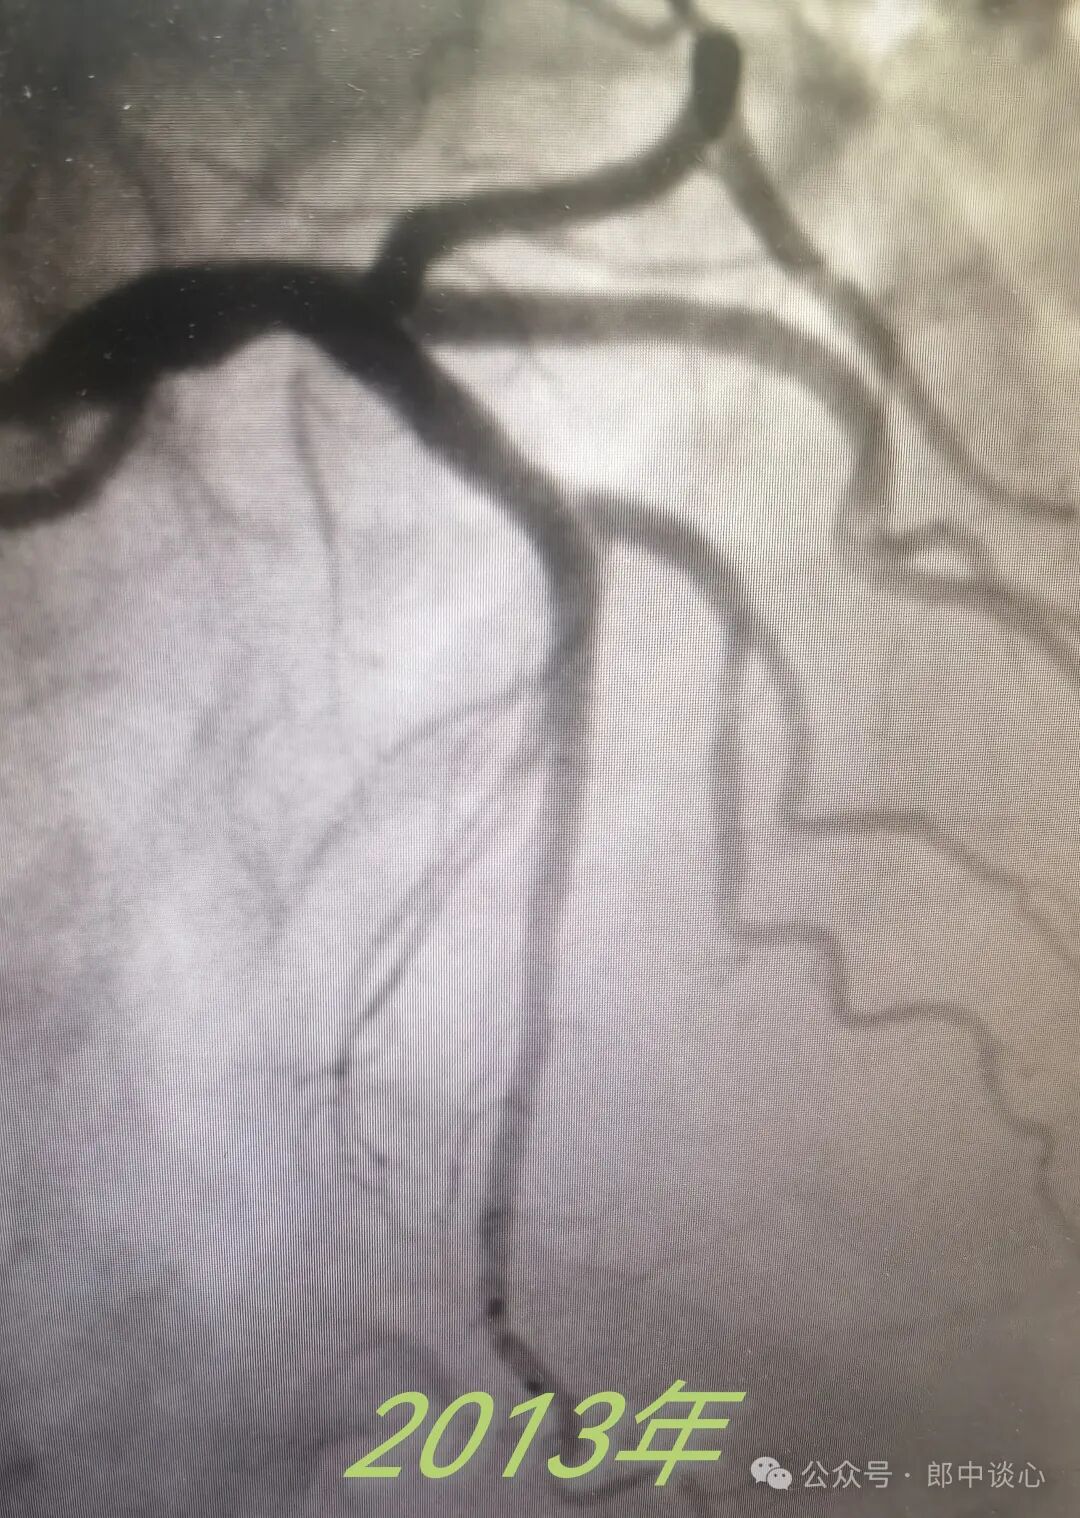

他在2012年前就有支架植入史,我在电脑上还能看到他在2012年、2013年做的造影。

看起来,当时的左冠还不错。